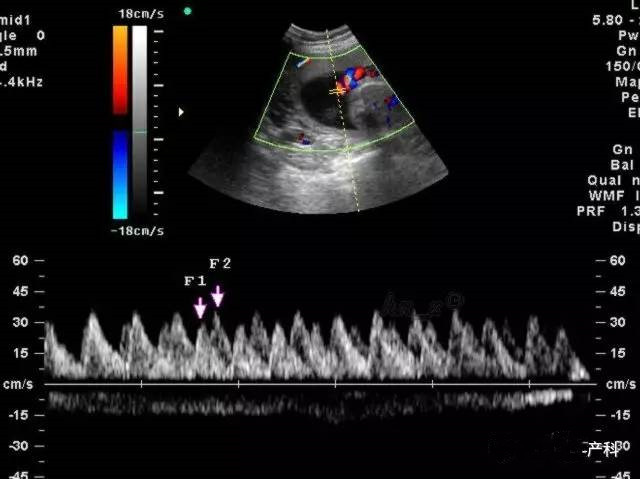

正常值跟怀孕的周数有关,主要有三项,以S/D值为主要指标,多以妊娠晚期S/D值小于或等于3.0作为正常值.脐血流和孕周时间有着密切的关系,一般随着孕周的增加,脐血流呈下降趋势,脐血流正常值在24周时其平均值为3.5,上限为4.25,超过此值为异常。可以使用脐动脉血流检测仪,在胎儿肢体侧探测脐动脉血流,内置软件根据所测S/D,PI、RI、FUR血流指标将自动测出血流阻抗分级。

这些都是测定脐动脉血流阻抗(显示胎儿与胎盘之间循环状况)的指标。

RI:脐动脉血流阻力指数

S/D:脐动脉血流速度峰谷比

正常妊娠时胎儿的S/D、RI值随着妊娠时间推移呈降低趋势,尤其S/D值的变化是掌握胎儿发育是否正常的重要指标。